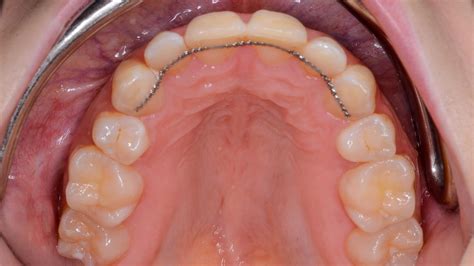

Retenedores Dentales Fijos

Los retenedores dentales fijos permanecen en la boca todo el tiempo porque están pegados a la parte posterior de los dientes. Normalmente este tipo de retenedor se coloca detrás de los seis dientes inferiores delanteros.

A veces los ortodoncistas pueden empezar con un retenedor pegado y cambiar a un retenedor Hawley o Essix después de seis meses a un año. Puede ser muy difícil usar el hilo dental en los dientes adheridos; debe usar el hilo dental para hacerlo correctamente.

Ventajas y Desventajas de los Retenedores Fijos

- Ventaja: mantiene tus dientes saludables. No puede ser visto por otros.

- Desventaja: difícil de usar el hilo dental. Puede cortar o alterar la lengua. A veces la cera dental puede ser conveniente.